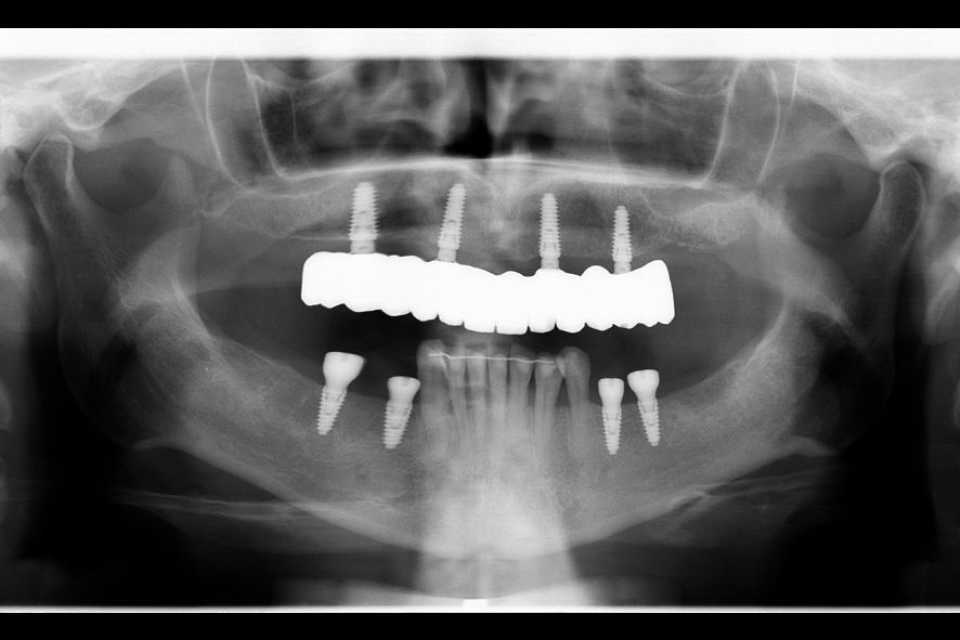

În urma examenului de specialitate, s-a constatat prezența unei punți totale la nivelul maxilarului și a două lucrări vechi la nivelul mandibulei, în zonele laterale premolar-molar. Dintii stâlpi prezentau multiple pungi parodontale, leziuni apicale și mobilitate accentuată.

Împreună cu pacienta, am optat pentru un tratament complex, realizat într-o singură ședință. S-au efectuat extracțiile dinților parodontotici, chiuretajul pungilor parodontale și inserarea a 4 implanturi Mega-Gen AnyRidge la nivelul maxilarului. Cu ajutorul capelor multiunit, s-a reușit protezarea imediată, prin aplicarea unei lucrări provizorii din acrilat, la doar 24 de ore de la intervenție. După 2 luni, tratamentul a fost finalizat prin realizarea unei lucrări definitive, înșurubabile, din ceramică pe suport de zirconiu, cu 12 elemente.

La nivelul mandibulei, reabilitarea zonelor laterale premolar-molar s-a realizat prin inserarea a câte două implanturi pe fiecare parte, protezate după 2 luni cu două lucrări din ceramică pe suport de zirconiu, cimentate. Dintii restanți ai mandibulei au fost conservați după tratamentul parodontal și solidarizați printr-o contenție linguală.